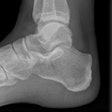

Oxford team focuses on outcome in ankle injuries